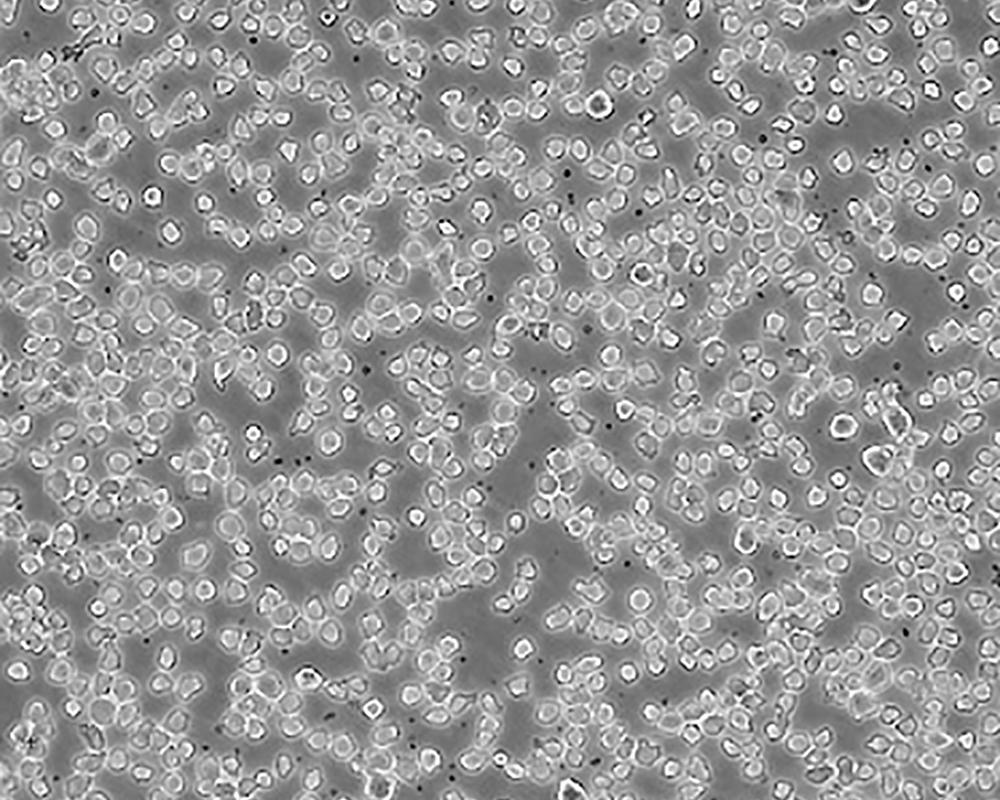

THP-1

中文名稱 人單核細胞白血病

組織來源 急性單核細胞白血??;男性

生長特性 suspension

形態(tài)特征 monocyte

細胞描述 該細胞從一名1歲的患有急性單核細胞性白血病的男孩的外周血中分離建立。該細胞可以吞噬乳膠顆粒和激活的紅細胞,細胞膜和胞漿內(nèi)均沒有免疫球蛋白,表達C3R和FcR;可受佛波酯TPA誘導向單核系方向分化;可作為轉染宿主。